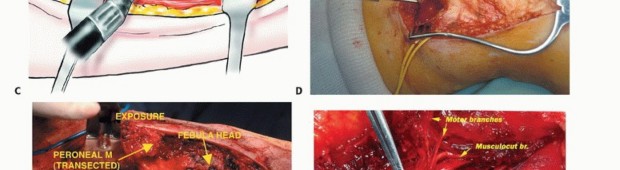

الاستئصال من النوع الثاني (Type II Resection):

- الإشارة: يُستخدم لعلاج الأورام الغرنية عالية الدرجة، والتي عادةً ما يكون لديها تدمير قشري كبير مع امتداد خارج العظم.

- الإجراء: يشمل إزالة الشظية القريبة والمفصل الظنبوبي الشظوي، والحجرات العضلية الأمامية والجانبية، والعصب الشظوي، والشريان الظنبوبي الأمامي بشكل كامل. يتطلب هذا النوع ربط الشريان الظنبوبي الأمامي وقد يتطلب أيضًا التضحية بالشريان الشظوي.

- الحفاظ: لا يتم الحفاظ على العصب الشظوي والشريان الظنبوبي الأمامي.

الشق الجراحي (القطع الجراحي)

يُستخدم "الشق الشظوي النفعي" (utilitarian fibular incision)، والذي يسمح بكشف واستئصال الأورام في جميع مستويات الشظية. يمتد هذا الشق من العضلة ذات الرأسين فوق مفصل الركبة، فوق الجزء الأوسط من الشظية، إلى الأمام باتجاه قمة الظنبوب، ثم ينحني خلفيًا وبعيدًا إلى الكاحل. يسمح هذا بتطوير سدائل جلدية عضلية أمامية وخلفية كبيرة.